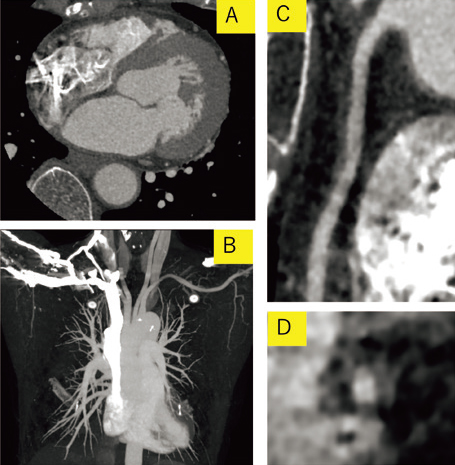

図1 造影剤のみで検査を行った画像

A:冠動脈CT Axial画像

B:大動脈MIP画像

C:右冠動脈CPR画像

D:右冠動脈短軸画像